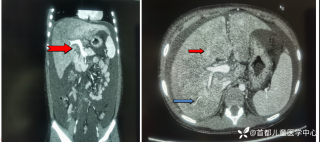

灼见|如果是你,如何处置山东男孩(多器官切除病例)

西地兰vip普外科医师

文/西地兰 特别声明:所有观点仅代表个人言论 特别声明:与当事双方均无利益相关 山东男孩,目前全网沸沸扬扬,看过一些观点,直言不讳地说,大多偏颇。要么一股脑地指责医方的全责,甚至有说千万别在县医院看病。要么又为医方无休止的遮羞,认为这样的手术在县医院做下来已经非常了不起。而我想到的是,以后面临类似的病例,我们怎么办?那么我们不如来一次专业的病案讨论。既然是事后讨论,难免有事后诸葛亮的感觉,但是假如下一次,同行们遭遇这样的病例,如何处置?这是医疗行业所面临的问题。希望我整理的这些思路和相关病例,对同行们有所帮助!就目前的资讯外界不足以判断是否需要急诊,如果需要急诊,那么只能根据术中所见进行处理,

玩耍被撞后10岁男孩被诊断有肿瘤,多器官切除 当地卫健局:医院存在问题,已立案

丁香医小白普外科医师

2023年10月26日,来自山东菏泽市成武县的小烨和他家人的命运被彻底改变了。这个原本阳光、可爱的小男孩在一次意外被撞击后,在医院检查出了腹腔内存在肿瘤,并在手术中被切除了包括十二指肠、胰腺、大部分胃和小肠等多个器官。此后便无法再像正常人一样吃饭、喝水,活着要靠长期静脉注射营养液。一份2024年12月由第三方机构出具的司法鉴定意见书显示,当时给小烨做手术的成武县人民医院在该医疗行为中存在过错,与小烨的损害后果之间存在因果关系,建议医疗过错在损害后果中的原因力大小为同等原因。此外,另一份由成武县卫生健康局在2025年9月28日发出的书面答复中显示,成武县人民医院存在24小时内未完成病历;手术知情

目前知道的消息,第一,术前发现一个血肿,然后做增强CT发现一个占位,没说血肿与肿瘤的关系,术后病理没有描述肿瘤出现破裂出血,大概率就一个小血肿,我就不明白当地主任凭哪个指针去给这小孩开急诊刀的?哪个指南告诉他需要急诊开?第二,诊断不明确他想的不是进一步检查,一边观察一边进一步查,他反而选择腹腔镜探查,这个探查的指针在哪?第三,腹腔一个血肿,没有活动性出血,没有血压心率出现问题,为什么要开腹进去碰它?不能等血肿吸收再明确肿瘤性质吗?第四,1点进腹,3点病理结果出来,按这个时间还算顺利,应该还没出事,孩子还算平稳,病理是低度恶性,切了就治愈,他一年能开几台这手术,就敢继续做,拿孩子练手。第五,后面